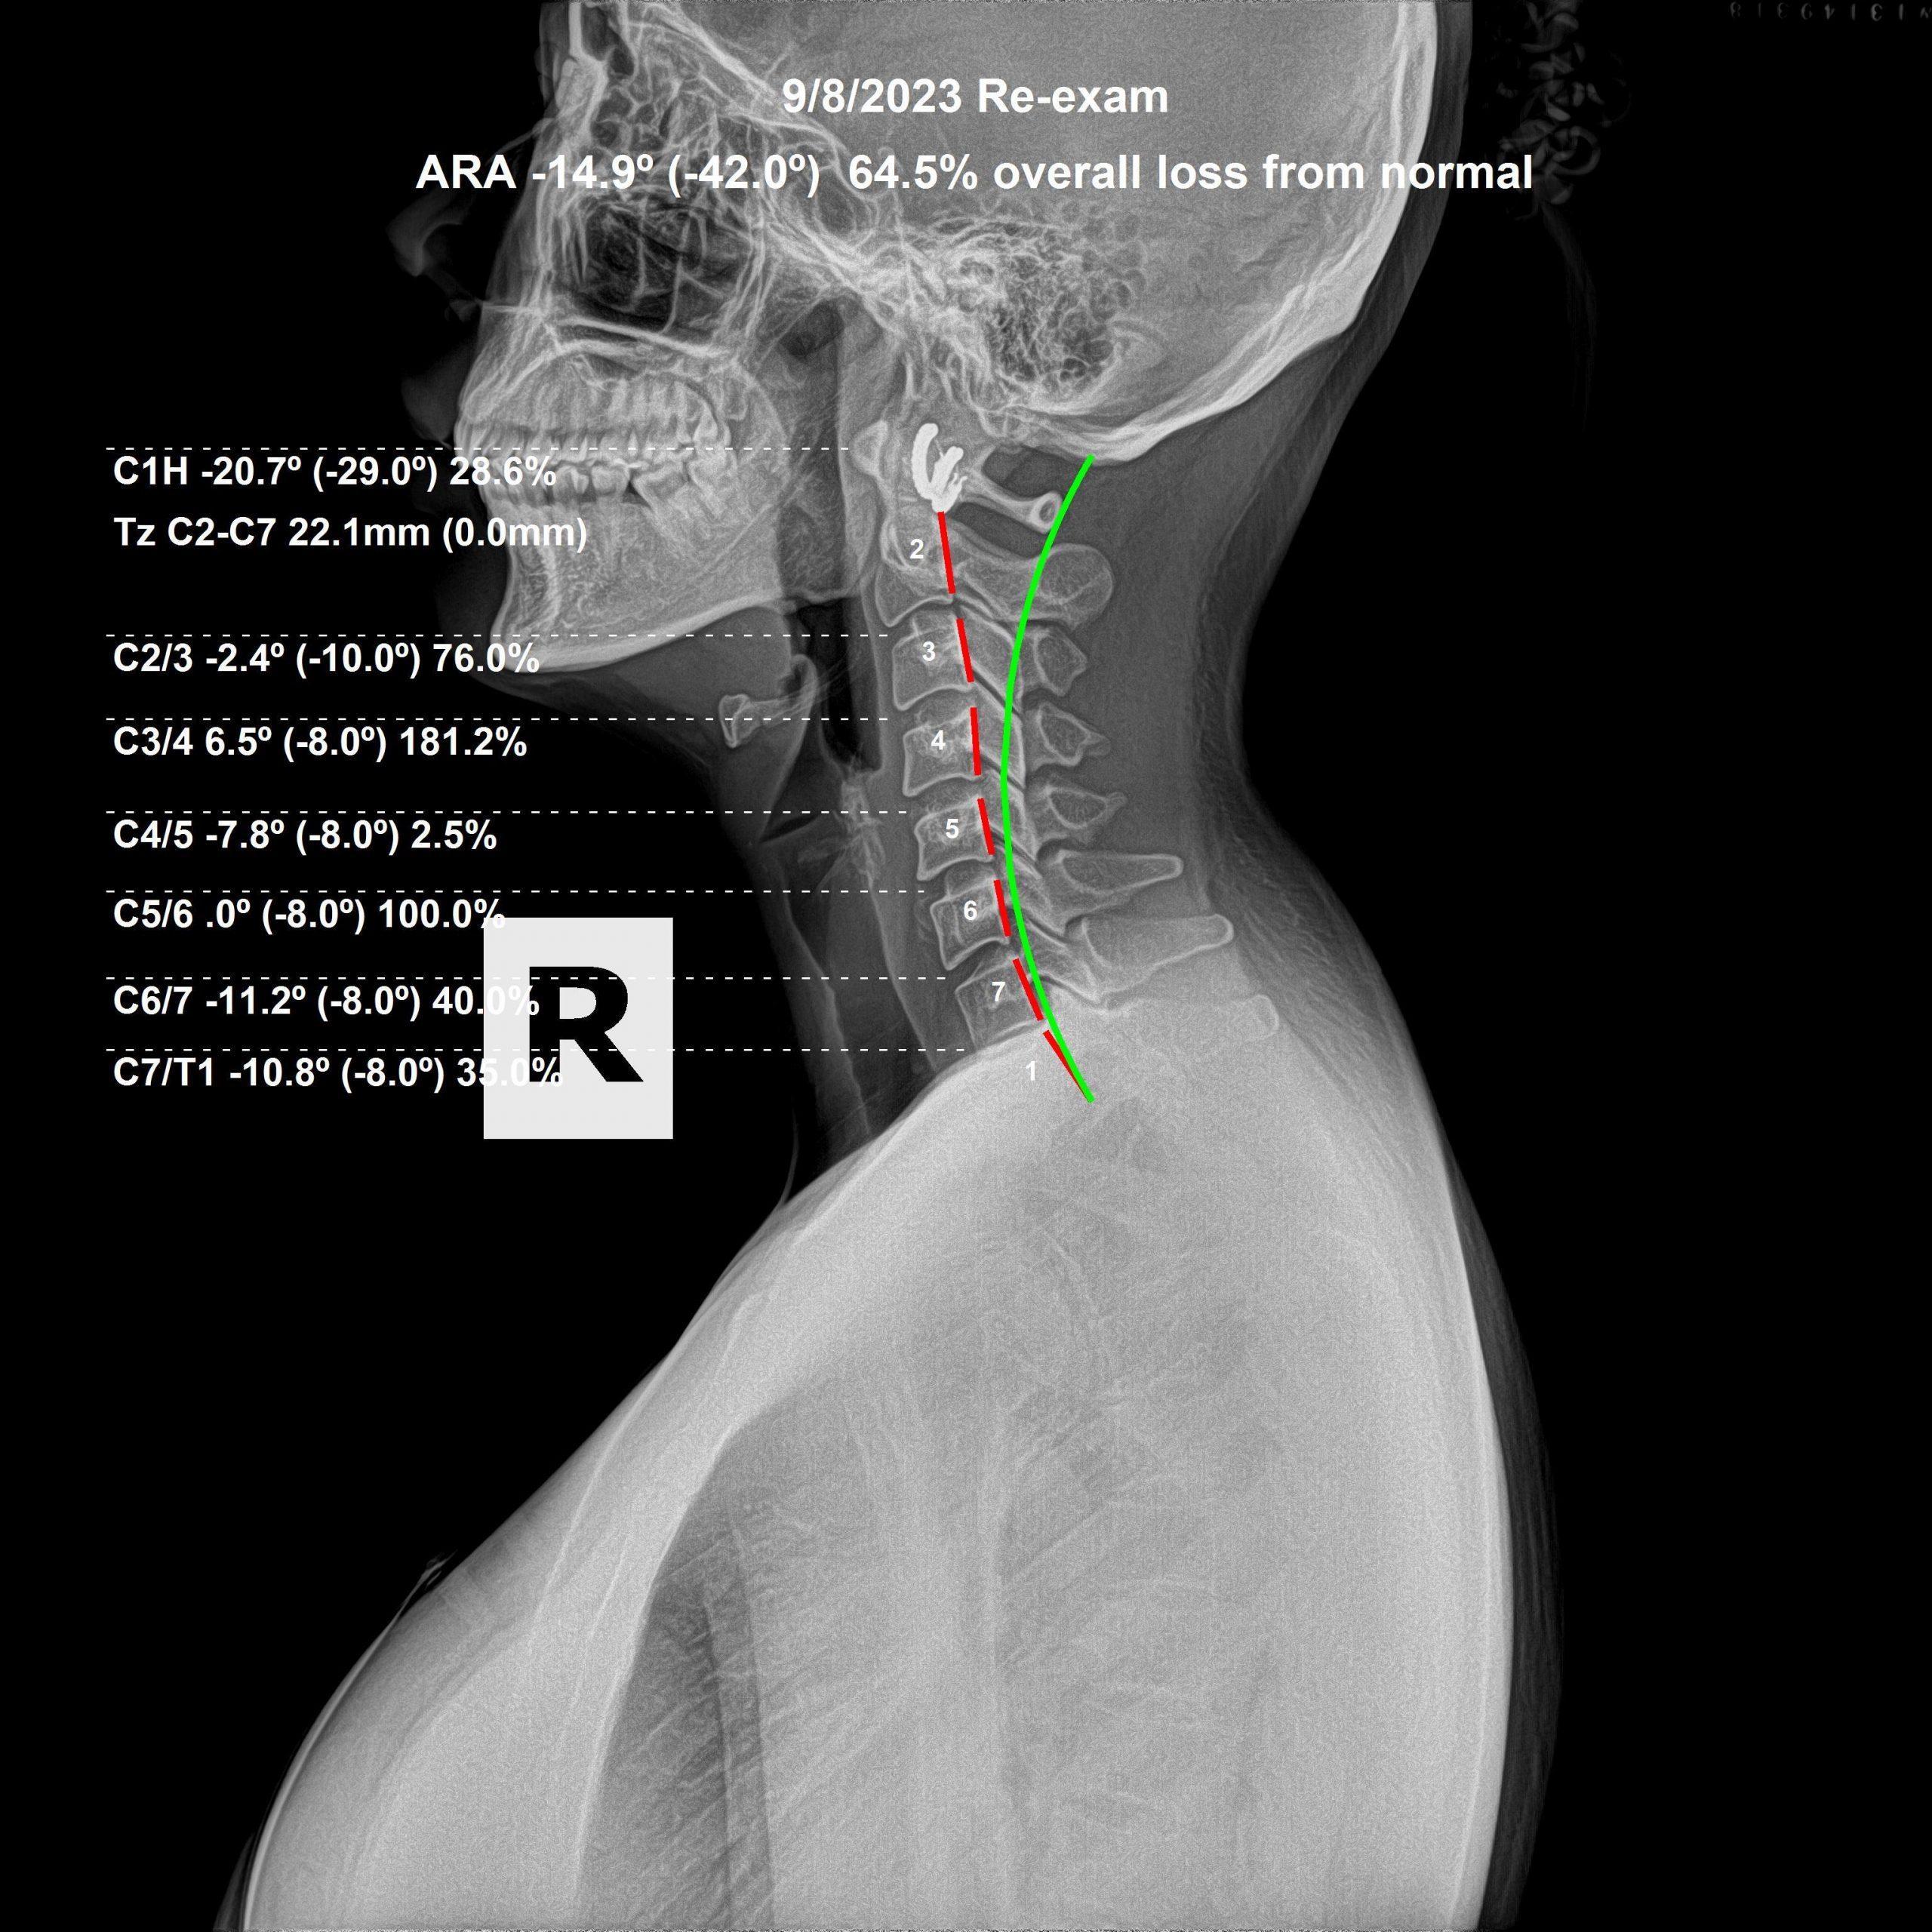

We take initial X-Rays to determine length of corrective care, as well as follow up x-rays to determine continuation of care. Spinal alignment restoration is key to stimulating restoration of function.